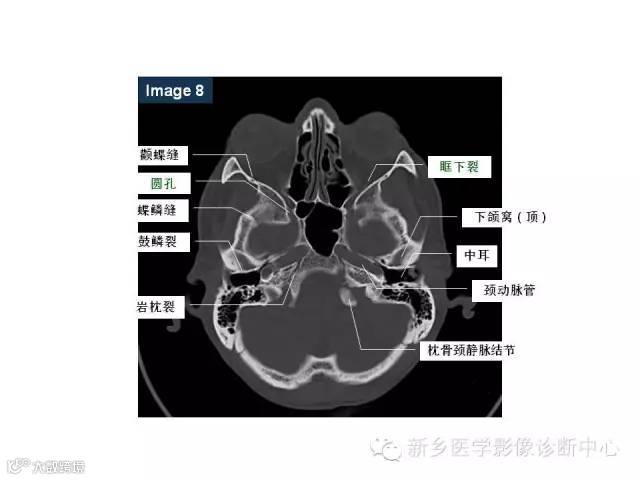

颅底孔道解剖详解

值得收藏!